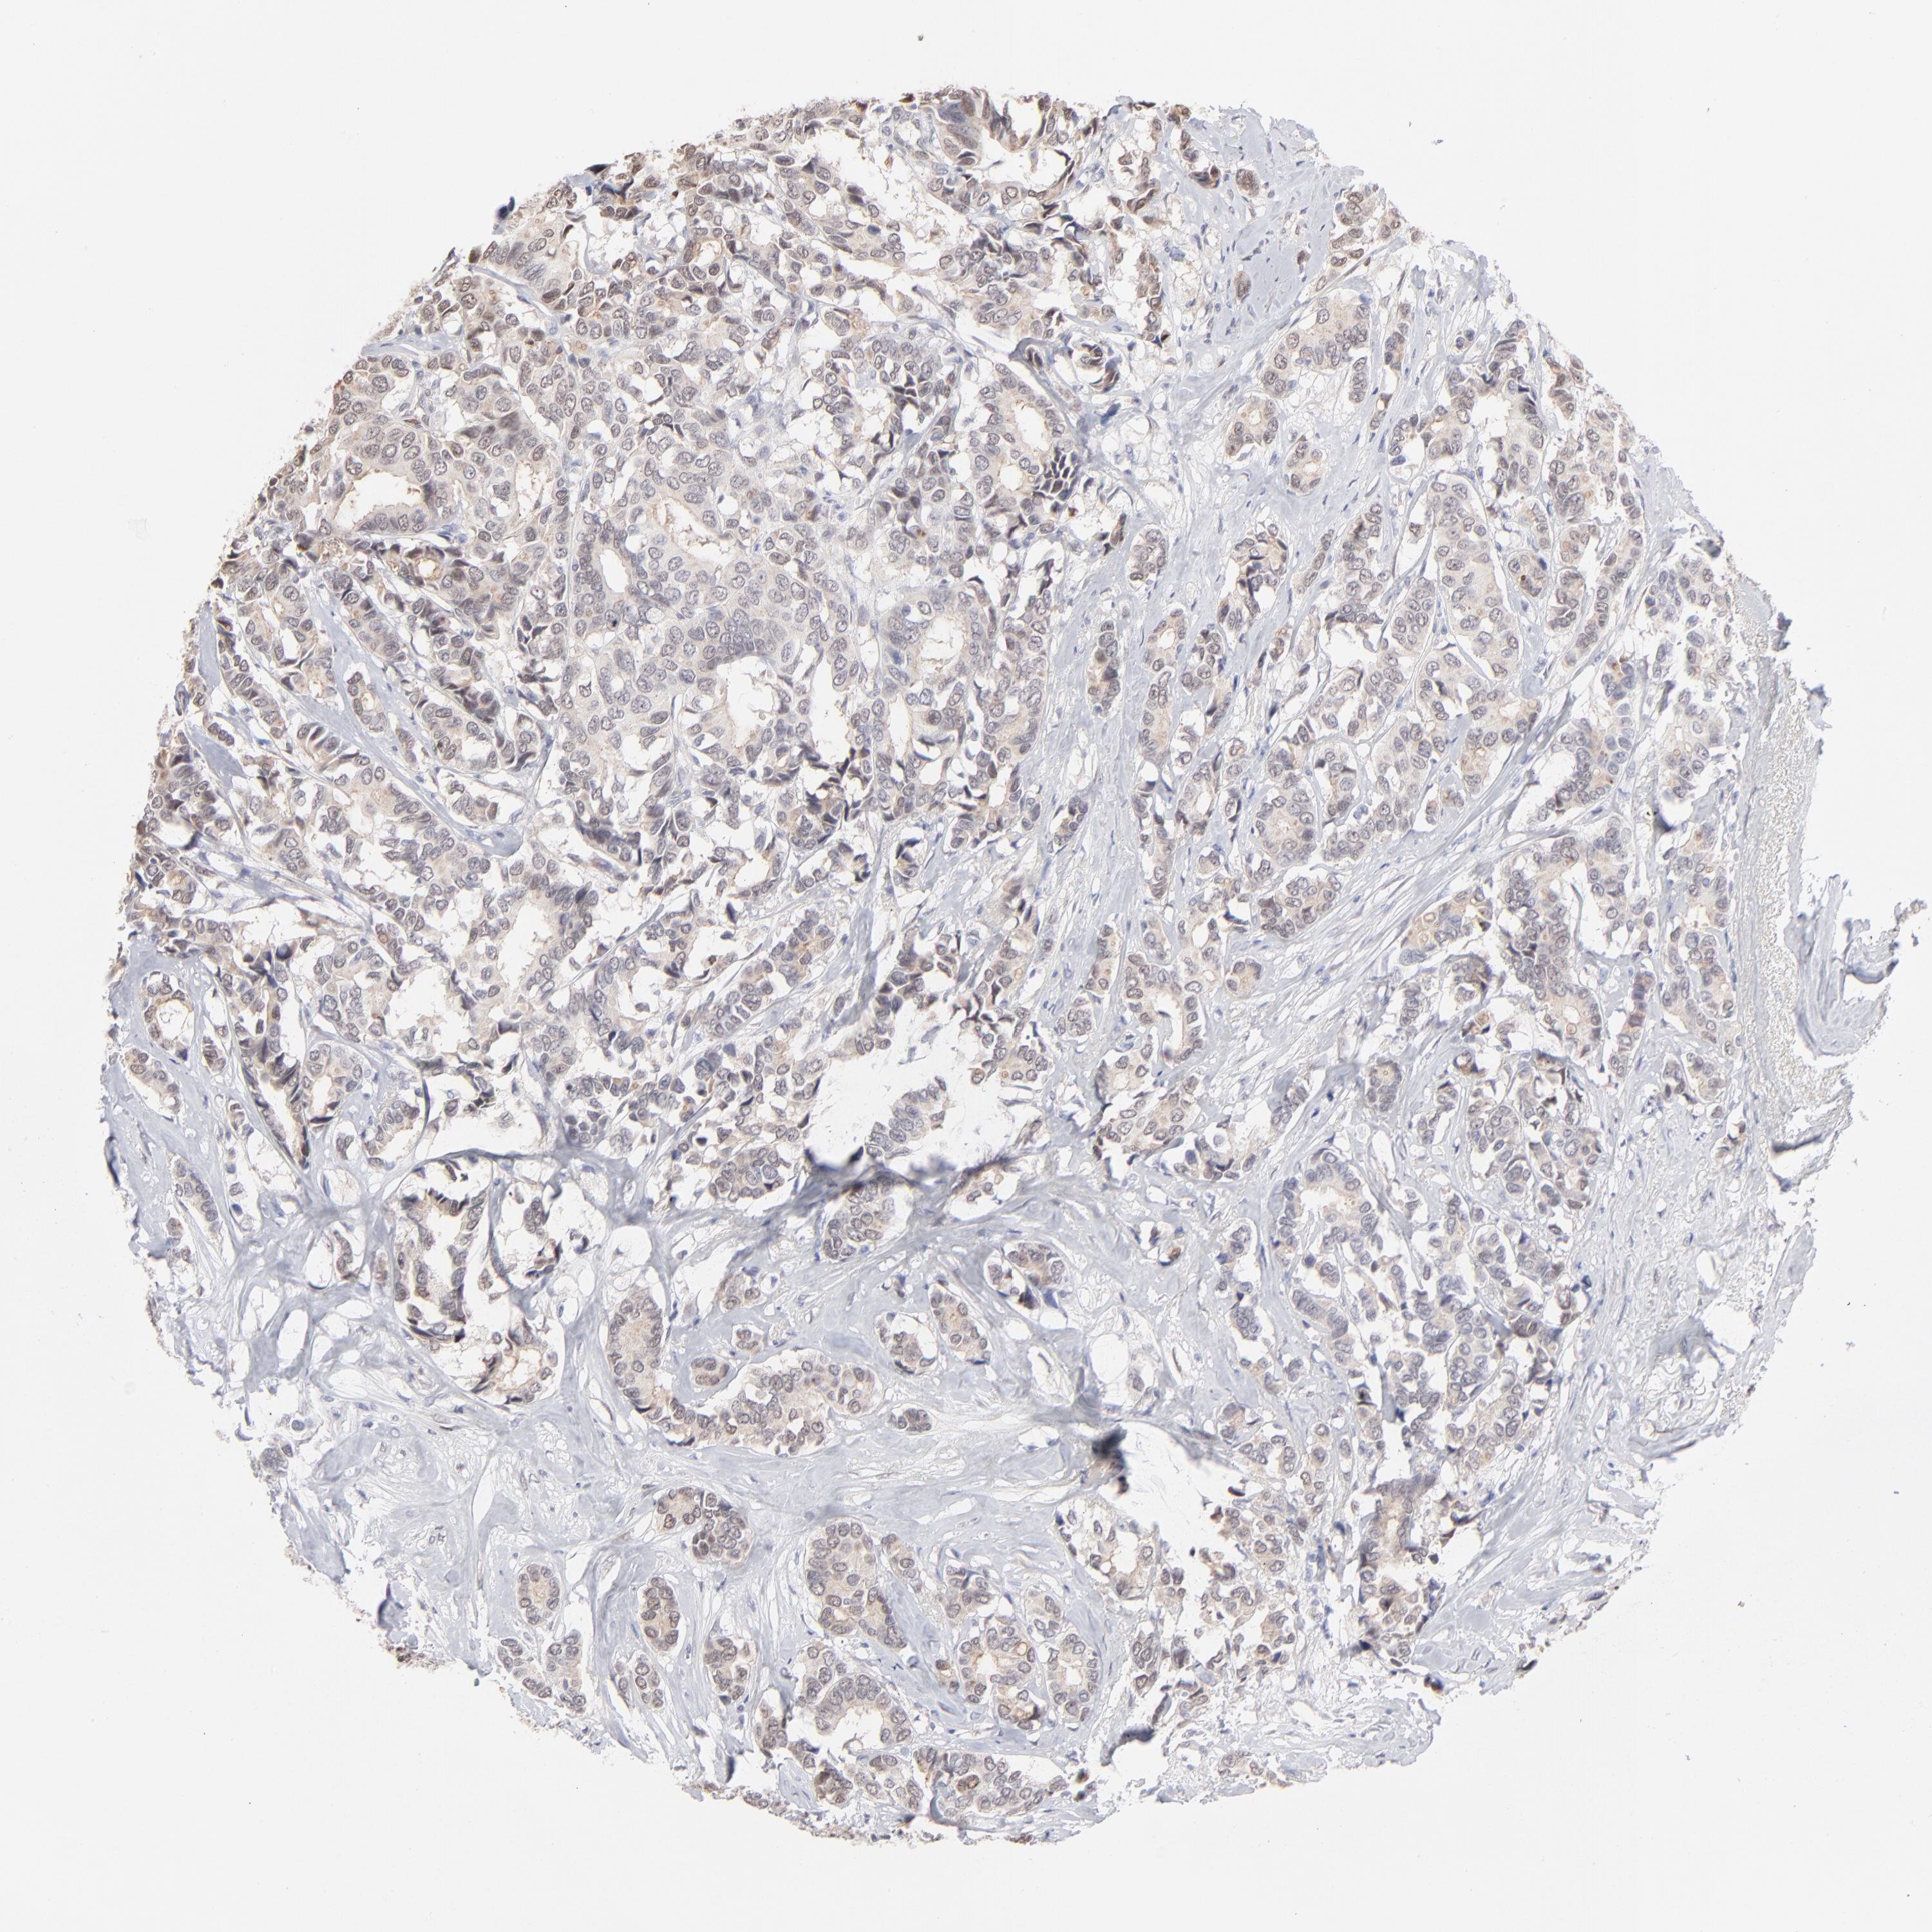

CANCER BREAST CANCER Show tissue menu

BRCA TCGA BRCA VALIDATION PROTEIN EXPRESSION